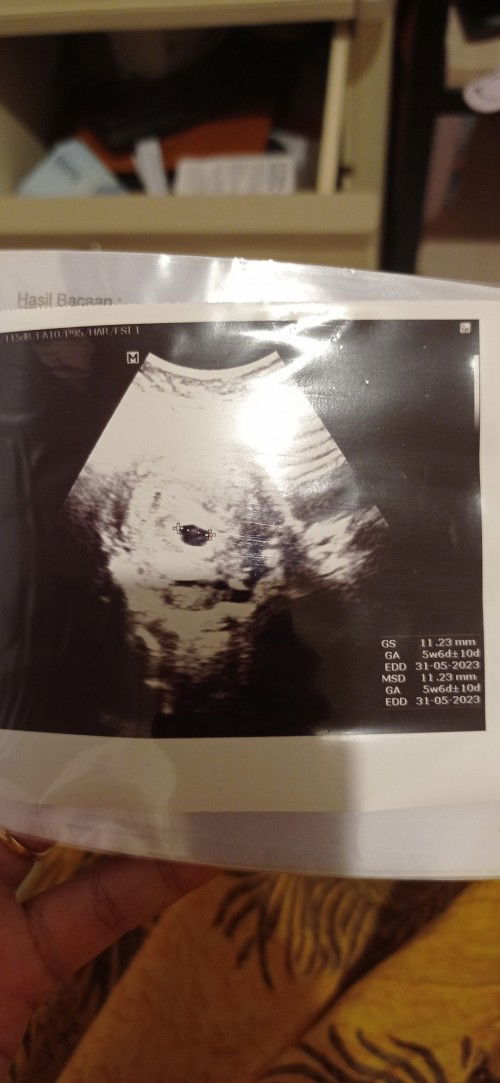

Posisi kantung janin

Sharing yuk bun... Ini hasil usg aku kemarin, usia kehamilan 5w, kata dokter posisi kantung kehamilan agak kebawah, wajar ngga sih bun diusia kehamilan segitu terus posisinya agak kebawah? Saya agak kuatir bun soalnya ini kehamilan pertama